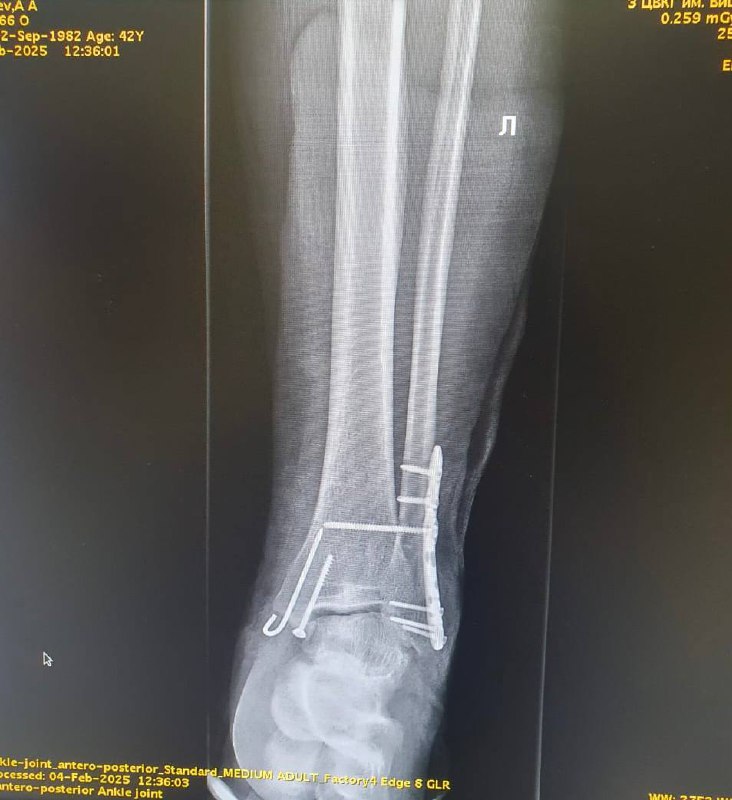

Дальше — скорая помощь 🚑, городская больница в Красногорске, из которой пришлось очень быстро сбежать (отец, мама и брат провели настоящую спецоперацию). Потом операция, при которой мне вставили железные пластины и кучу винтов и шурупов, что еще больше приблизило меня к Железному человеку 🦸Теперь до апреля буду дома на костылях 🩼 , а потом долгий процесс восстановления.